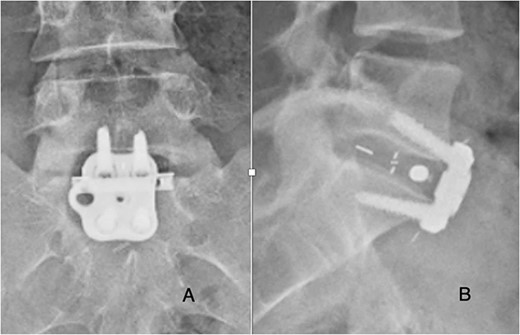

She was followed until 12 weeks post-operatively, with complete resolution of symptoms and did not appear for any appointments past 12 weeks. Radiographs obtained at follow-up demonstrated stable cage and plate placement (Fig. 3).

Post-operative posterior-anterior (A) and lateral (B) films demonstrate ALIF cage and plate placement.